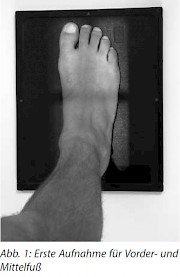

1. Aufnahme (Abb. 1)

- Bein und Knie gestreckt halten, während der andere Fuß einen Schritt zurückgenommen wird, um die Balance zu halten.

- Zentrierung: senkrecht auf Mittelfuß und Kassettenmitte

- Strahlengang: dorsoplantar

- Einblenden auf Objekt, d. h. vom Vorfuß bis zum Unterschenkel. Bleizeichen für die Seitenbezeichnung.